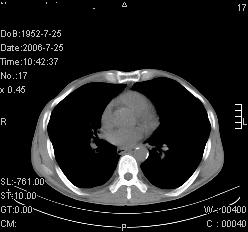

患者,男,54岁,咳嗦,咳痰20天。抗炎治疗2周。现esr76mm/h,目前患者症状明显好转,但发现两次ct片未见明显变化。两次分别做与7.25、7.31。第一次诊断右肺上叶炎症累计胸膜。大家看,从影像上内排除结核吗?

结核的可能性非常大,右上肺病变应该考虑干酪性肺炎。理由:

1.纵隔内多发淋巴结肿大。

2.esr76mm/h。

3.虽经抗炎治疗肺窗病灶有所吸收、减小,但纵隔窗病灶形态、密度、范围无明显变化。如果是单纯的大叶性肺炎,“抗炎治疗2周,目前患者症状明显好转”病灶应该基本消散了,至少也处于吸收消散期,密度变淡、范围变小。同时本病例所示其内的密度不均匀,见多发大小不一空洞样影也不符合大叶性肺炎吸收消散期表现。

病灶特点:片状 索条 结节混杂影,部分融合,密度不均,广泛累及相应胸膜.

临床治疗;二周未吸收.但症状好转.

多考虑:肺结核.